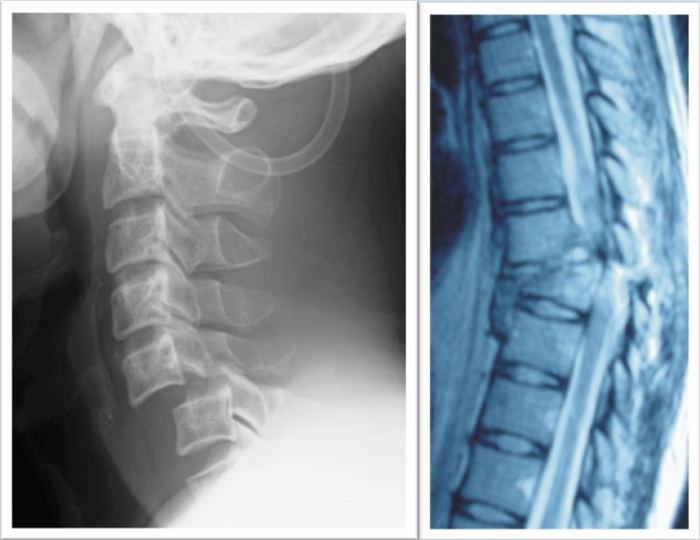

「iPS細胞を用いた脊髄損傷の再生医療」